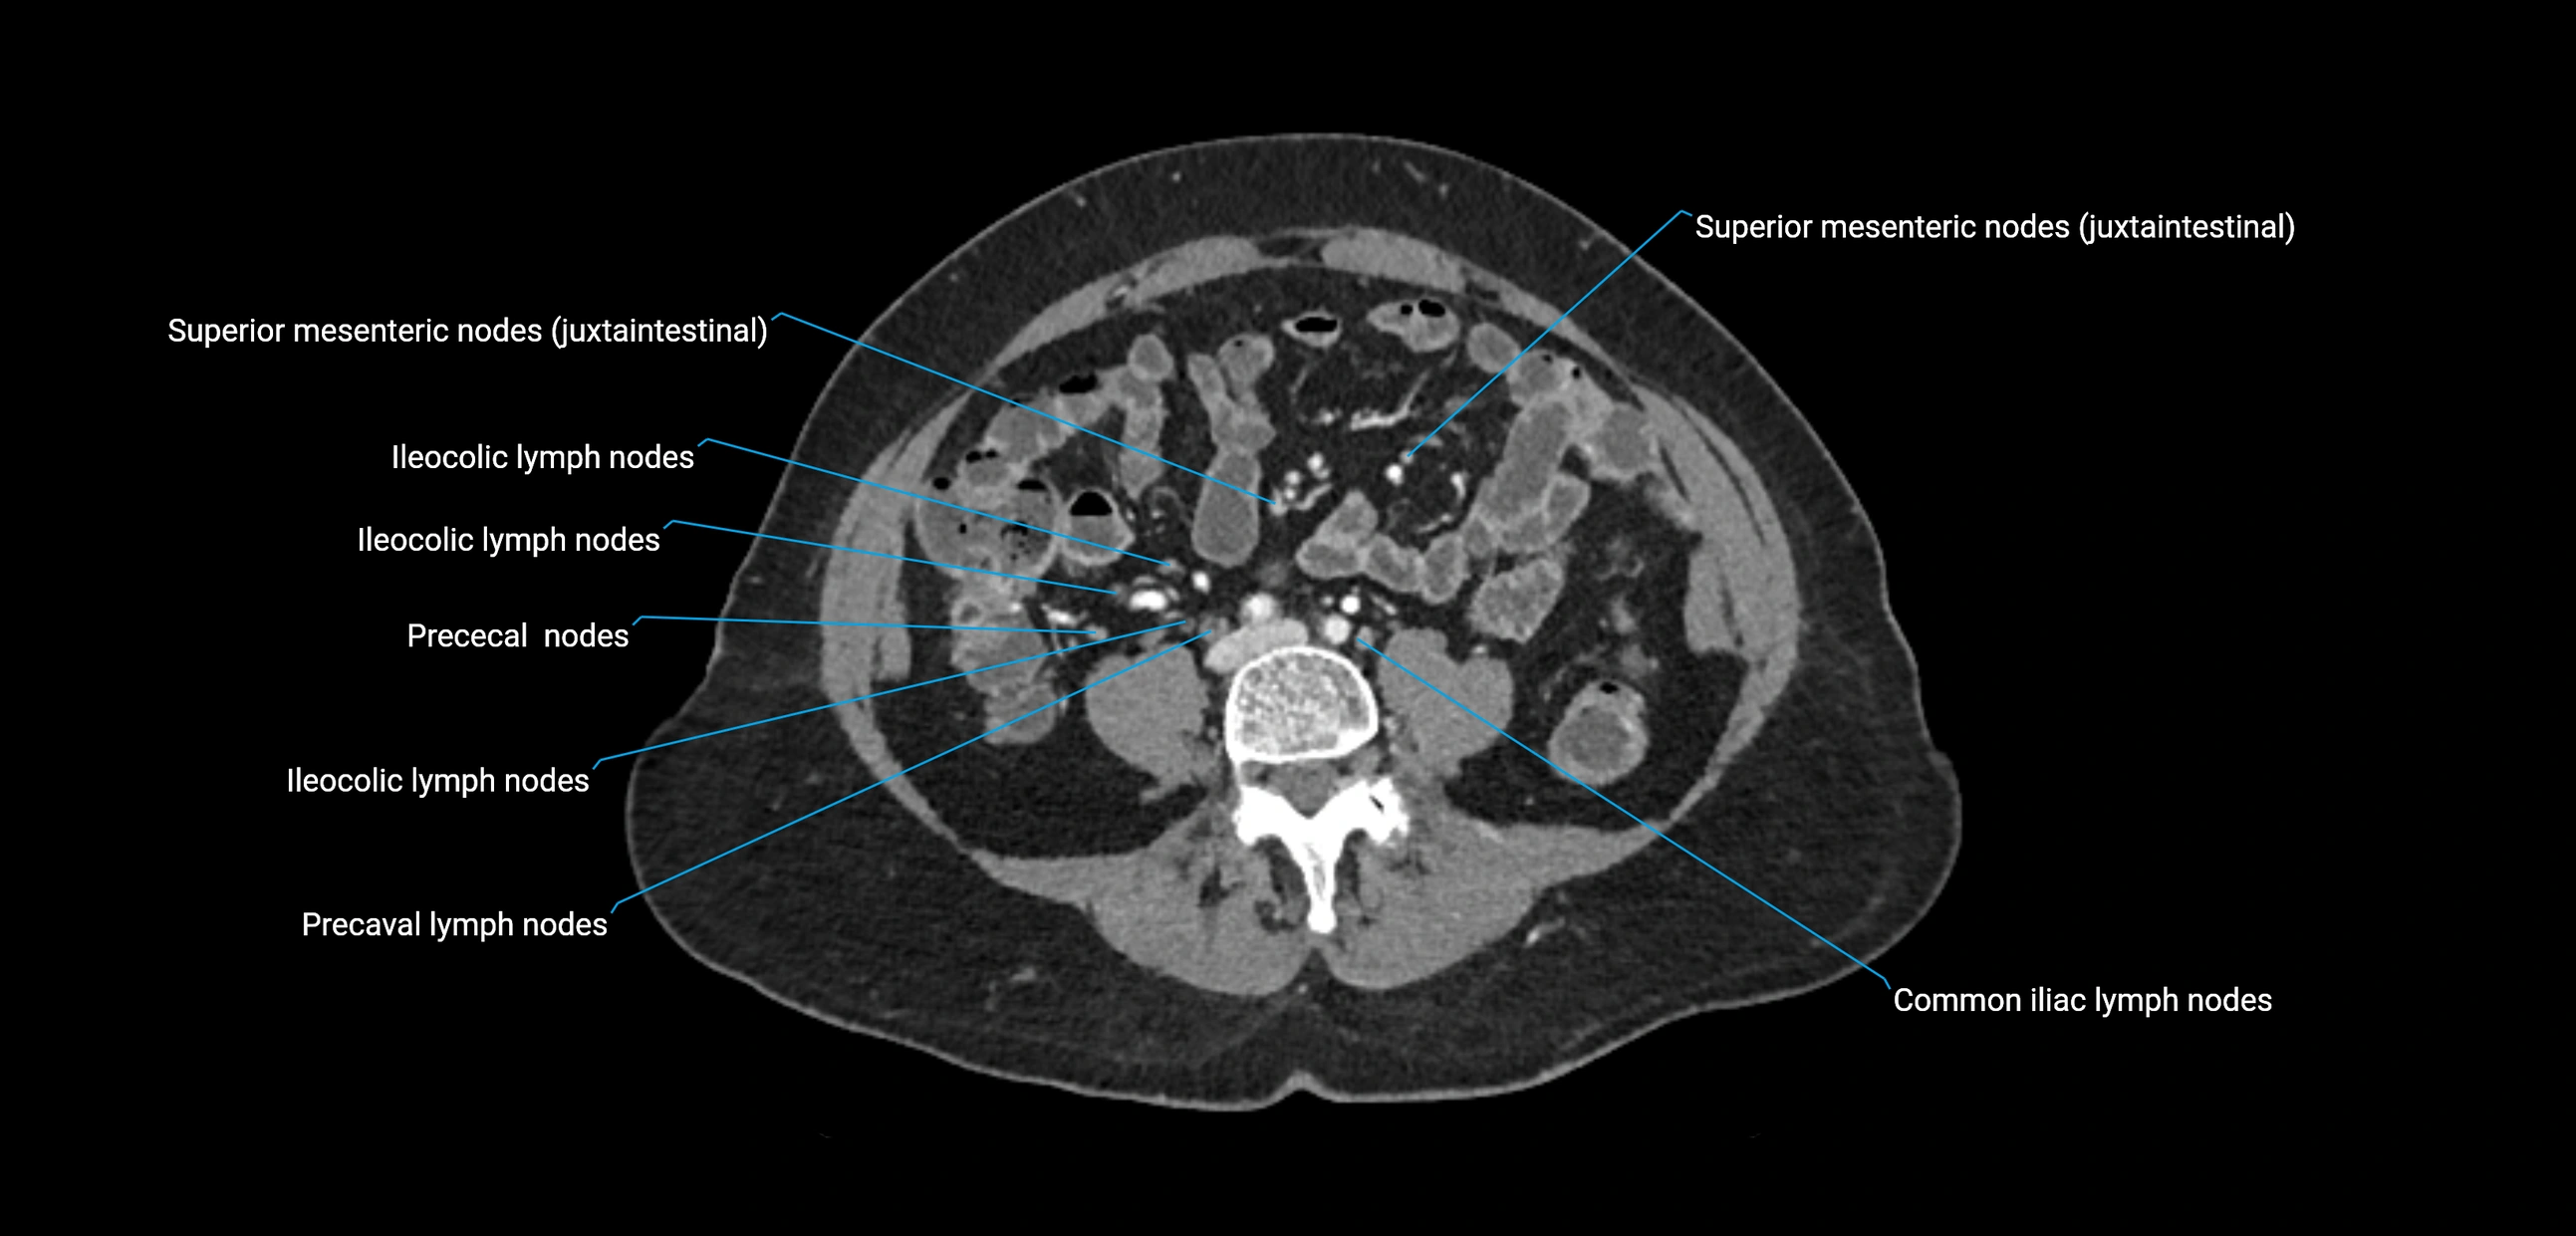

CT image

image